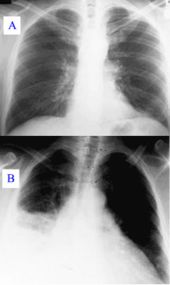

An important test for pneumonia in unclear situations is a chest x-ray. Chest x-rays can reveal areas of opacity (seen as white) which represent consolidation. Pneumonia is not always seen on x-rays, either because the disease is only in its initial stages, or because it involves a part of the lung not easily seen by x-ray. In some cases, chest CT ( computed tomography) can reveal pneumonia that is not seen on chest x-ray. X-rays can be misleading, because other problems, like lung scarring and congestive heart failure, can mimic pneumonia on x-ray. Chest x-rays are also used to evaluate for complications of pneumonia ( see below.)

The discovery of x-rays made it possible to determine the anatomic type of pneumonia without direct examination of the lungs at autopsy and led to the development of a radiological classification. Early investigators distinguished between typical lobar pneumonia and atypical (e.g. Chlamydophila) or viral pneumonia using the location, distribution, and appearance of the opacities they saw on chest x-rays. Certain x-ray findings can be used to help predict the course of illness, although it is not possible to clearly determine the microbiologic cause of a pneumonia with x-rays alone.